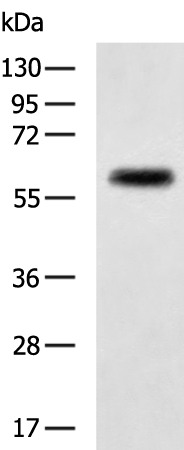

分类: 科研抗体货号: P08917别名: HCC-8应用: WB,IHC反应种属: Human, Mouse